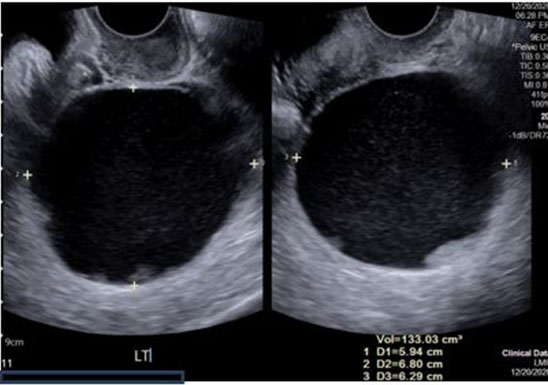

Pelvic ultrasound showed normal appearing ovaries without sonographic evidence of ovarian torsion. Color flow and spectral Doppler demonstrated normal arterial and venous blood flow and waveforms in the bilateral ovaries. Medial and adjacent to the left ovary was an elongated anechoic cystic structure measuring 4.85 × 5.45 × 3.58 cm (Figure 1). Further imaging was performed to rule out other causes of acute abdomen. Computed tomography (CT) of the abdomen and pelvis showed no acute abdominal or pelvic process, small volume pelvic ascites and redemonstrated the small to moderate sized left hydrosalpinx. The gynecology service was then consulted for further evaluation and recommendations for management.

Figure 1: Transvaginal ultrasound imaging of left hydrosalpinx approximately 4.85 × 5.45 × 3.58 cm (Case 1).